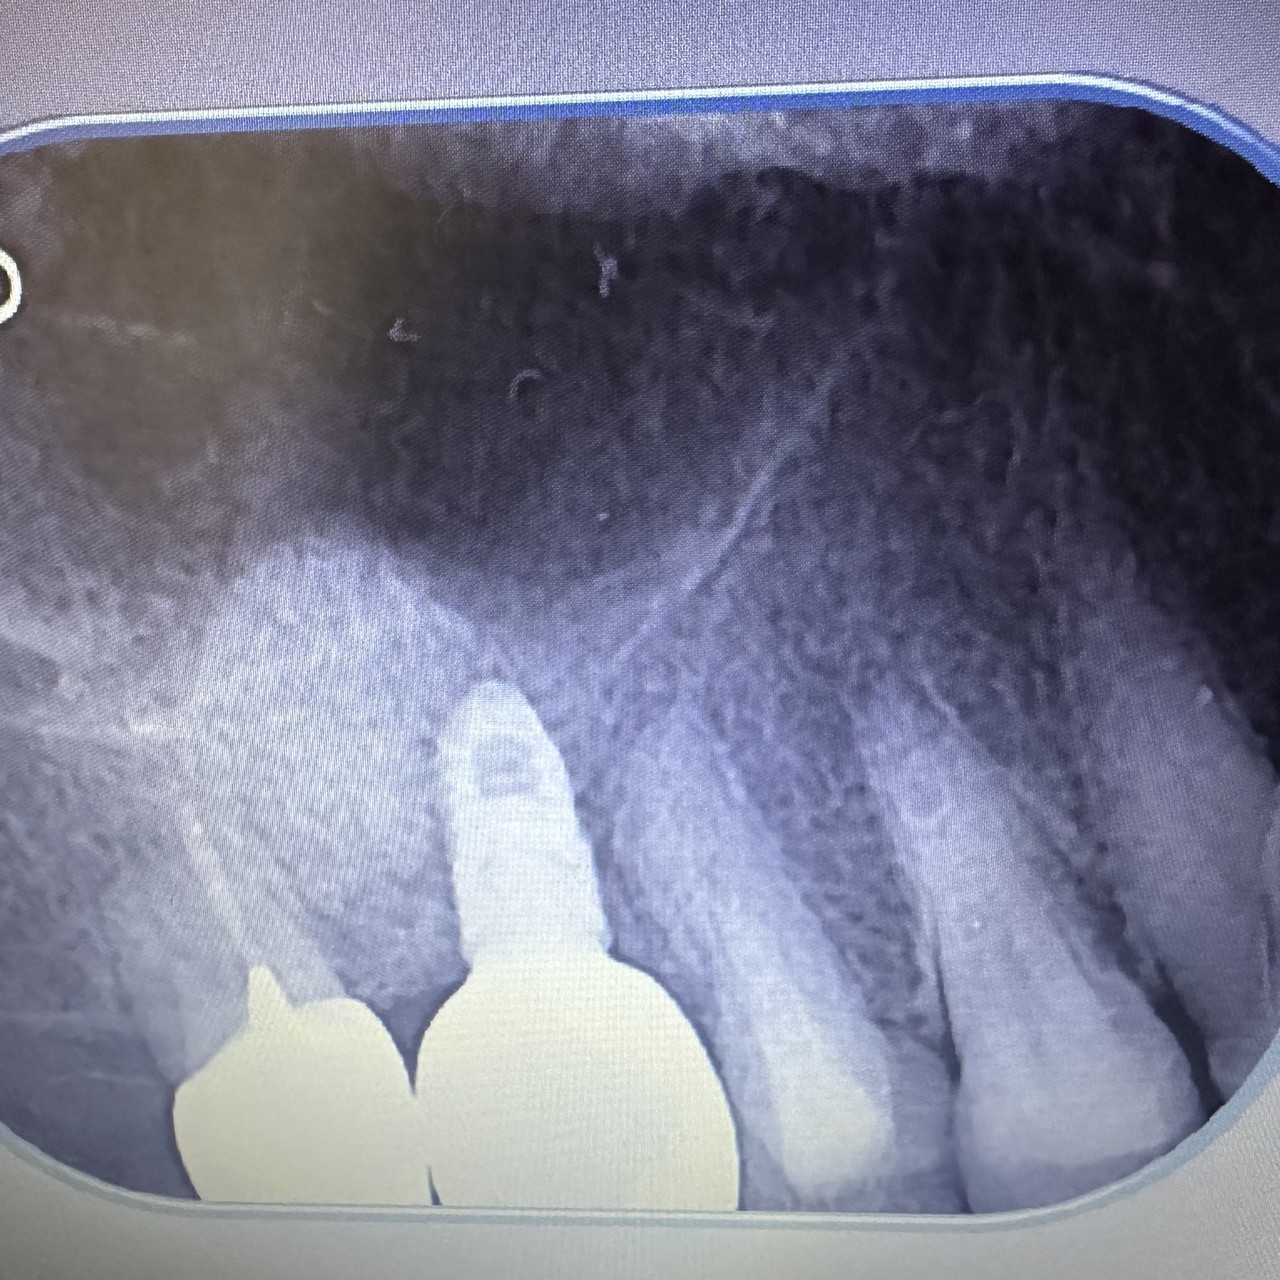

インプラント治療には外科手術が必須です。しかし手術の際に誤って神経や血管を傷つけてしまうと、重大な事故につながることもあります。そのため、一般的な歯科治療以上に綿密な検査・治療計画が必要です。

そこで当院は正確かつ安全なインプラント手術を実現するため、歯科用CT検査を実施。取得したデータを元に、事前に手術のシミュレーションを行っています。

手術前のシミュレーション

歯科用CT検査で得たデータをシミュレーションソフトに取り込むと、患者さまのお口の中で通常見えないところまでを3D画像でリアルに再現できます。この画像で以下の情報を確認します。

• あごの骨の量

• 周りの歯の根の位置

• 周囲にある神経や血管の位置

どの場所に、どのようにインプラントを埋め込むかをシミュレーションしながら、理想的なインプラント手術の計画を立てられます。